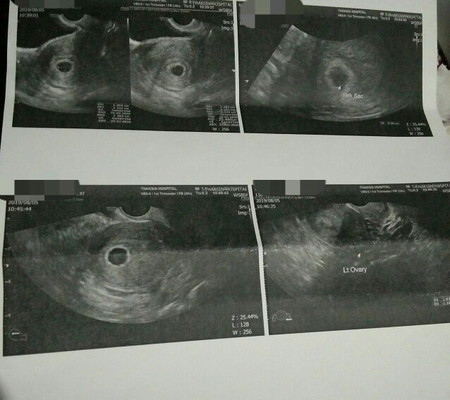

ซาวด์ครั้งแรกนับตามปจด.7วีคในใบซาวด์ได้6วีค1วันไม่แพ้ ช่วงแรกมีคัดเต้าหลังจาก6วีคคัดเต้าลดลงหมอนัดซาวด์อีก2สัปดาห์เป็นวันนี้ในใบซาวด์ได้6วีค5วันในถุงตั้งครรภ์ไม่มีการพัฒนาพรุ่งนี้ขูดมดลูก #คนท้องเท่ากับคนป่วยรักษากันไปตามอาการ #ท้องลมครั้งที่2